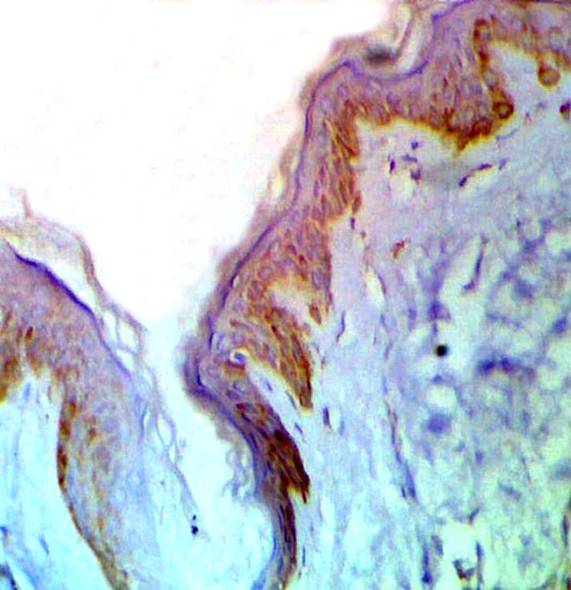

Fig 2: A case of LP showing strong expression of p53 in basal and suprabasal cell layers before treatment.(ABC, Meyer s HX counter stain x 200)